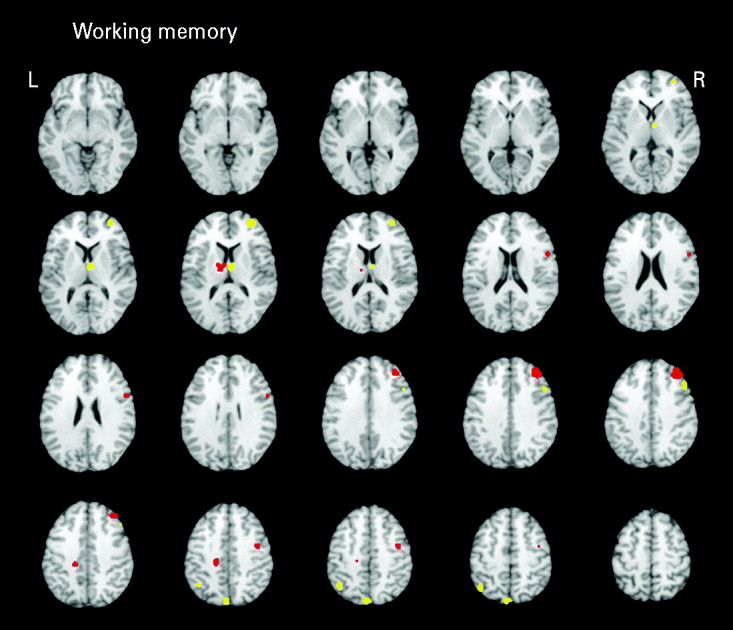

Seven studies (eight samples) used tasks categorized as primarily measuring working memory. Studies in the domain of working memory demonstrated mostly consistent activations with the all-studies functional activation map (Table 3 and Fig. 3). One notable difference from the all-studies activation map included the finding that, although both hypo- and hyperactivity were found in relatives, they were not found in overlapping middle frontal regions. This analysis suggests that the working memory studies contributed greatly to the all-studies activation map; however, it was the combination of all studies that led to the finding of hypo- and hyperactivity in the overlapping middle frontal regions.

Fig. 3. Above-threshold brain activations for contrasts of controls greater than relatives (red) and relatives greater than controls (yellow) for working memory studies. L, left; R, right.